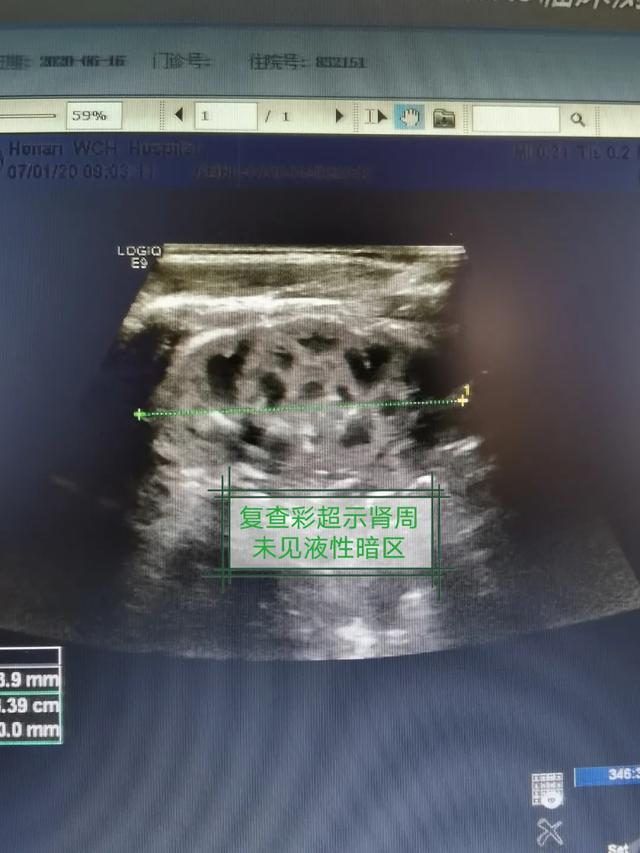

经过精心治疗与护理,术后 7 天复查彩超提示宝宝病情痊愈,而晓莉产后的各项指标也恢复正常,会阴切口愈合良好,一家人高高兴兴地办理了出院。